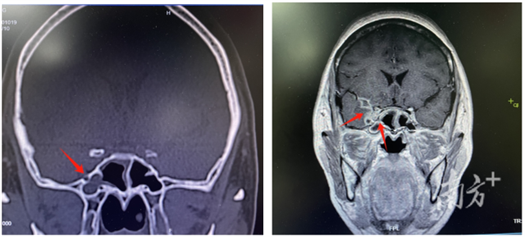

为寻求进一步诊疗,不久前,阿丽来到广东三九脑科医院。该院神经内一科副主任匡祖颖接诊时发现,患者的双眼微肿,脖颈强直,无法完成点头、摇头动作。从影像资料可见,患者颅内多处感染,右侧鼻腔与颅腔之间的骨质出现缺损。

影像提示:右侧鼻腔与颅腔间骨质缺损(左),颅内双侧海绵窦、垂体感染,累及右侧眼眶眶尖(右)。